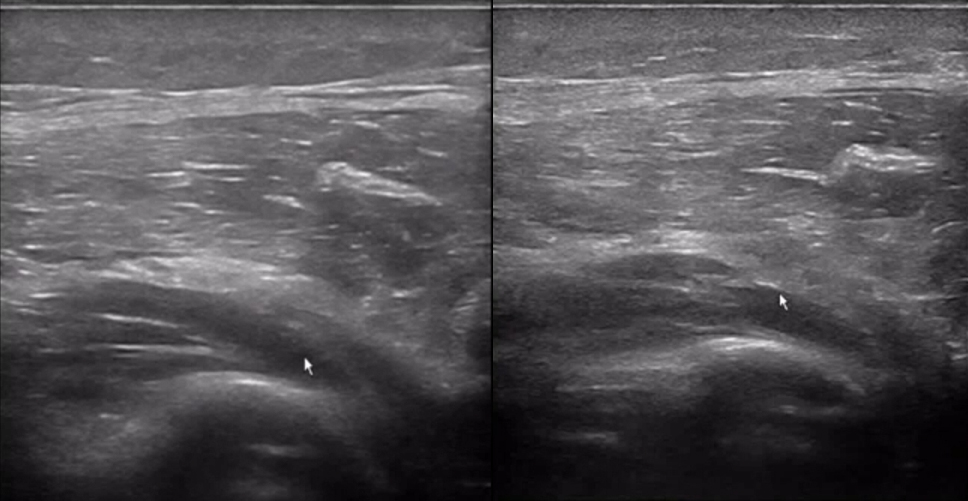

The patient experienced a noticeable snapping sensation in the wrist during active flexion of the interphalangeal joints.

?

Ultrasound detected a solid mass causing carpal tunnel syndrome.

This example showcases the role of POCUS in identifying and managing conditions like carpal tunnel syndrome, particularly in cases where traditional diagnostic methods might fall short.